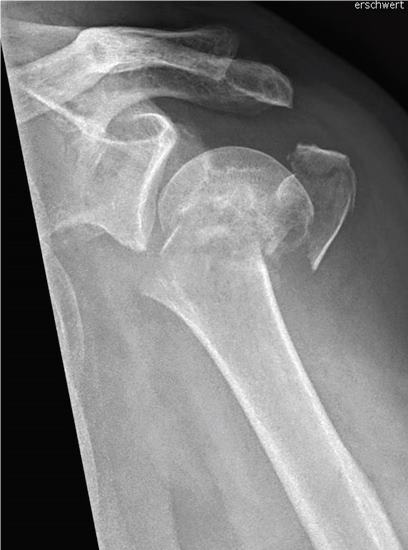

Einen weiteren Schwerpunkt in der Traumabehandlung stellt die Versorgung von Schulterbrüchen dar.

Während bei jüngeren Patienten die Rekonstruktion von Knochen und Gelenken im Vordergrund steht, führt bei älteren Patienten häufig der Gelenkersatz zur schnelleren Wiederherstellung der Beweglichkeit.